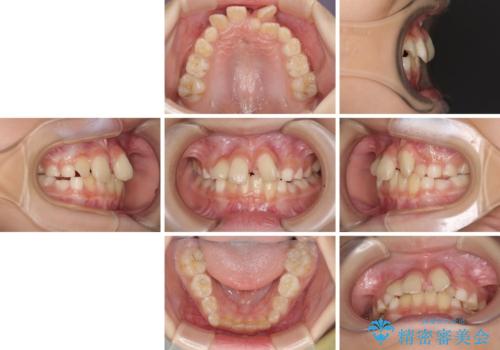

- 前歯の叢生を気にして来院された、小学校3年生女児の患者様です。

身長がやや低く、乳歯から永久歯への交換が少し遅い印象があったので、ワイヤー装置による1期矯正治療ではなく、乳歯も積極的に動かすことのできるインビザライン・ファーストにて治療を行うこととしました。

上顎前歯に過剰歯があったため、まずはその歯を抜歯し、傷が治癒したタイミングでインビザラインを発注することとしました。

インビザライン・ファーストは1.5年から2年程度の治療期間という制約がありますが、成人矯正(2期治療)をスムーズに行うための下準備期間として位置づけられており、2期治療を比較的安価かつ短期間で行うことができるようになります。